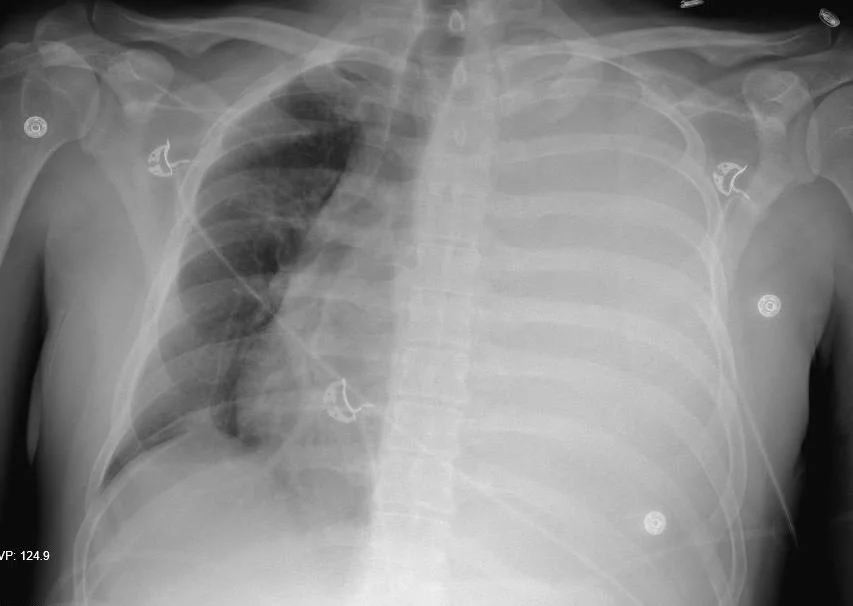

A 33 y.o. male presents with shortness of breath and stable vitals

Our patient underwent a thoracentesis of 2 L of bloody fluid.  His platelet count was 28,000 and he was given platelets and blood.  A thal quick was placed which subsequently clotted and a chest tube was placed draiining an additional liter.  Since each hemithorax can hold 40% of a patient’s blood volume, consideration was given to possible exsanguination from the chest tube and thoracic surgery was called.  Our patient stabilized and was treated for sepsis.  Imaging showed no active extravasation and widespread tumor with mets to bone and  pleura.  He was discharged home on hospice.